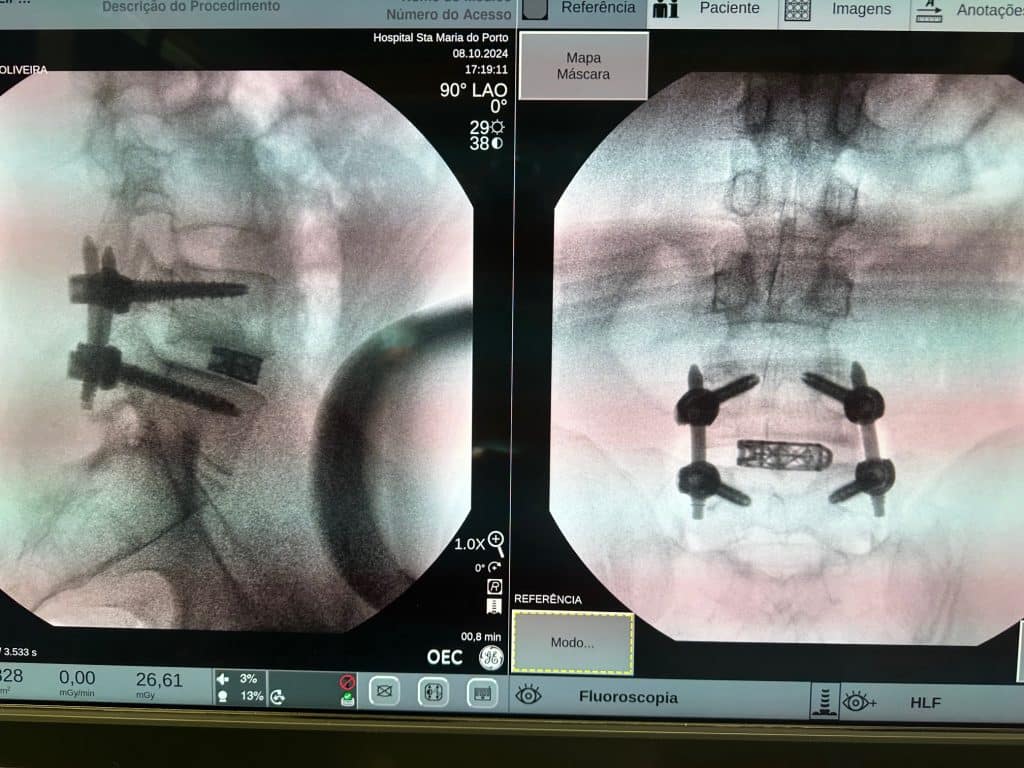

O equipamento combina as vantagens da imagiologia 2D, amplamente utilizada nos blocos operatórios, com a avançada tecnologia de imagem 3D, aumentando a eficiência e segurança dos procedimentos2. Este sistema, desenvolvido em colaboração com profissionais de saúde, possibilita uma visão tridimensional precisa, essencial para procedimentos de alta complexidade, como as cirurgias de coluna2. “Com este equipamento, é como se tivéssemos um TAC no bloco operatório, o que nos permite visualizar em tempo real o posicionamento dos implantes”, explica Rui Pinto.

Rui Pinto, pioneiro em cirurgia de coluna fundador da Sociedade Portuguesa de Patologia de Coluna (SPPC), destaca que “este equipamento representa uma melhoria substancial, especialmente nas cirurgias minimamente invasivas. A possibilidade de visualizar a anatomia em três dimensões permite-nos ter uma visão precisa das estruturas ósseas e colocar implantes com muito mais segurança. Na prática, podemos evitar erros que, no passado, poderiam resultar na necessidade de reintervenções. Com o equipamento, estamos a operar com uma margem de erro significativamente menor, quase inexistente.”